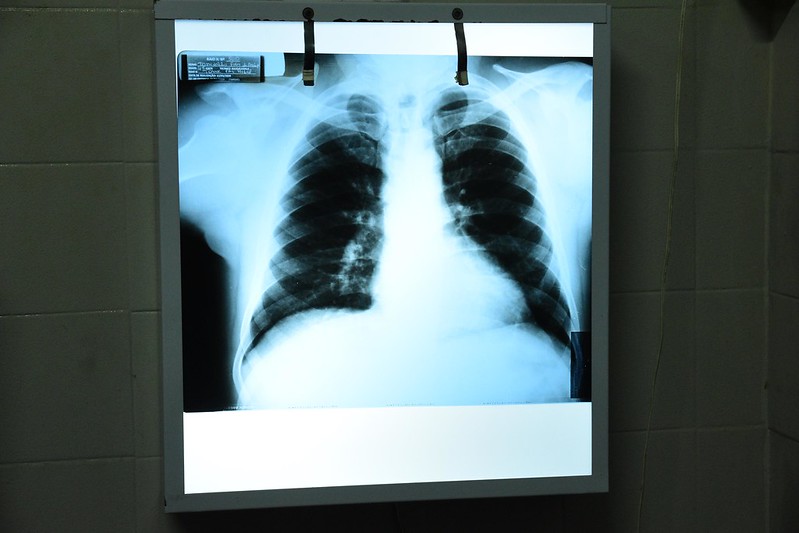

Em cerca de três semanas a Secretaria Municipal de Saúde conseguiu transpor os principais obstáculos. “Já estamos recebendo os pacientes com mais segurança porque recebemos equipamentos como o capote de chumbo, máscaras, luvas e filtros. Também recebemos películas grandes que são comuns, por exemplo, nos exames de tórax”, explica Carolina Santos, administradora da unidade.